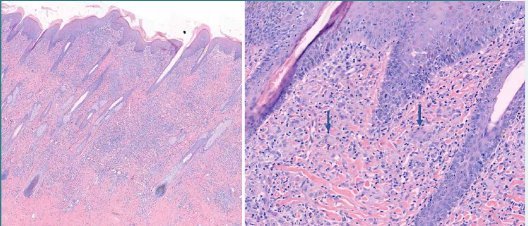

In dit geval is het histopathologische beeld eenduidig, waardoor de dierenarts een duidelijke diagnose krijgt. De huid vertoont hyperkeratose en is gering hyperplastisch verdikt. In de dermis is een diffuus celrijk granulomateus ontstekingsinfiltraat aanwezig met talrijke meerkernige reuscellen van het Langhans-type (fig 4). Dit beeld wijst op sarcoïdose.

Figuur 5. Huidbiopt met een uitgebreid ontstekingsinfiltraat in de dermis, bij een hogere vergroting (rechts) zijn veel meerkernige reuscellen van het Langhans-type zichtbaar.